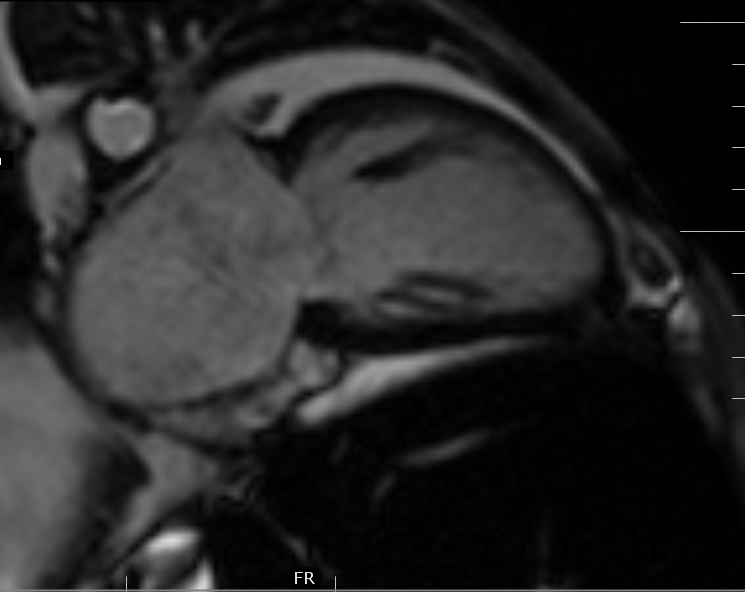

Myocardial Iron EstimationMRI Sumer's Radiology Blog Iron Supplements Mri Ferrous sulphate capsules contain approximately 65mg of iron and have not yet been identified as a source of artifacts for cardiac imaging previously. Meanwhile, many people take iron nutritional. On the basis of postmarketing surveillance data, the food and drug administration issued a black box warning. To summarize our single‐center safety experience with the off‐label use of ferumoxytol for magnetic. Iron Supplements Mri.

Myocardial Iron EstimationMRI Sumer's Radiology Blog Iron Supplements Mri • ferumoxytol is a small iron oxide particle with. To summarize our single‐center safety experience with the off‐label use of ferumoxytol for magnetic resonance imaging. The iron is in the form of a superparamagnetic iron oxide that causes t1, t2, and t2* shortening on magnetic resonance imaging (mri). Ferrous sulphate capsules contain approximately 65mg of iron and have not yet. Iron Supplements Mri.